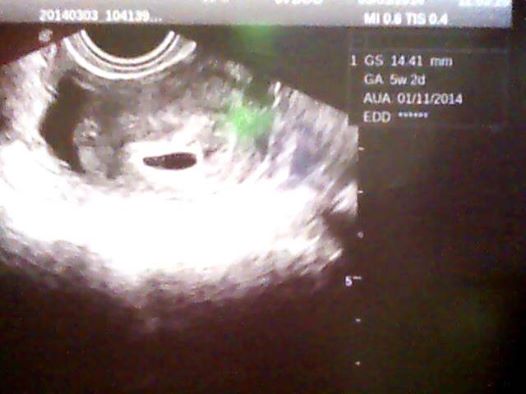

Autor: veveruska 10.3.2014 v 16:57

Ahojky holky,tak dneska jsem díky bolestem v podbříšku byla na kontrole a vše je ok mimi už je krásně vidět má necelých 7mm a srdíčko už taky krásně bije,dám sem fotku pro povzbuzení a všem vám držím palečky...jinak jsem dneska 6+3

No taky se divím se koukni na tu první fotku ta je z 5+3 a ta druhá z dneška a to je 6+3 za ten týden už to je krásně vidět a srdíčko bylo taky krásně vidět...mimochodem mám termín podle ultrazvuku přesně na 7. narozeniny mého druhého syna